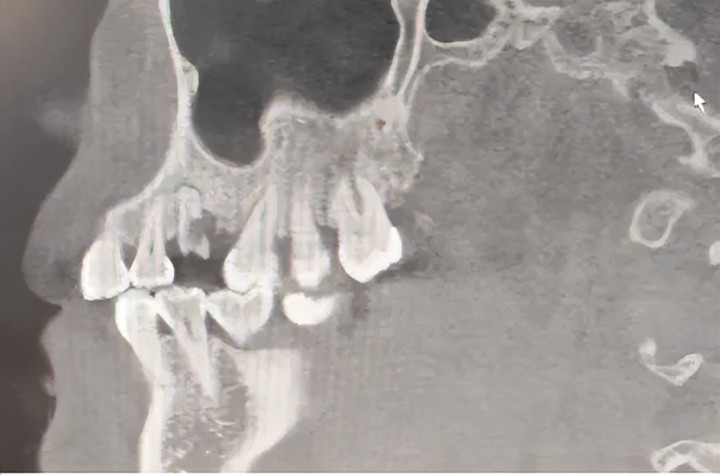

牙周病是牙齿的“隐形杀手”。当牙槽骨被炎症给与殆尽,牙齿松动得像风中的树叶,无法保留时。